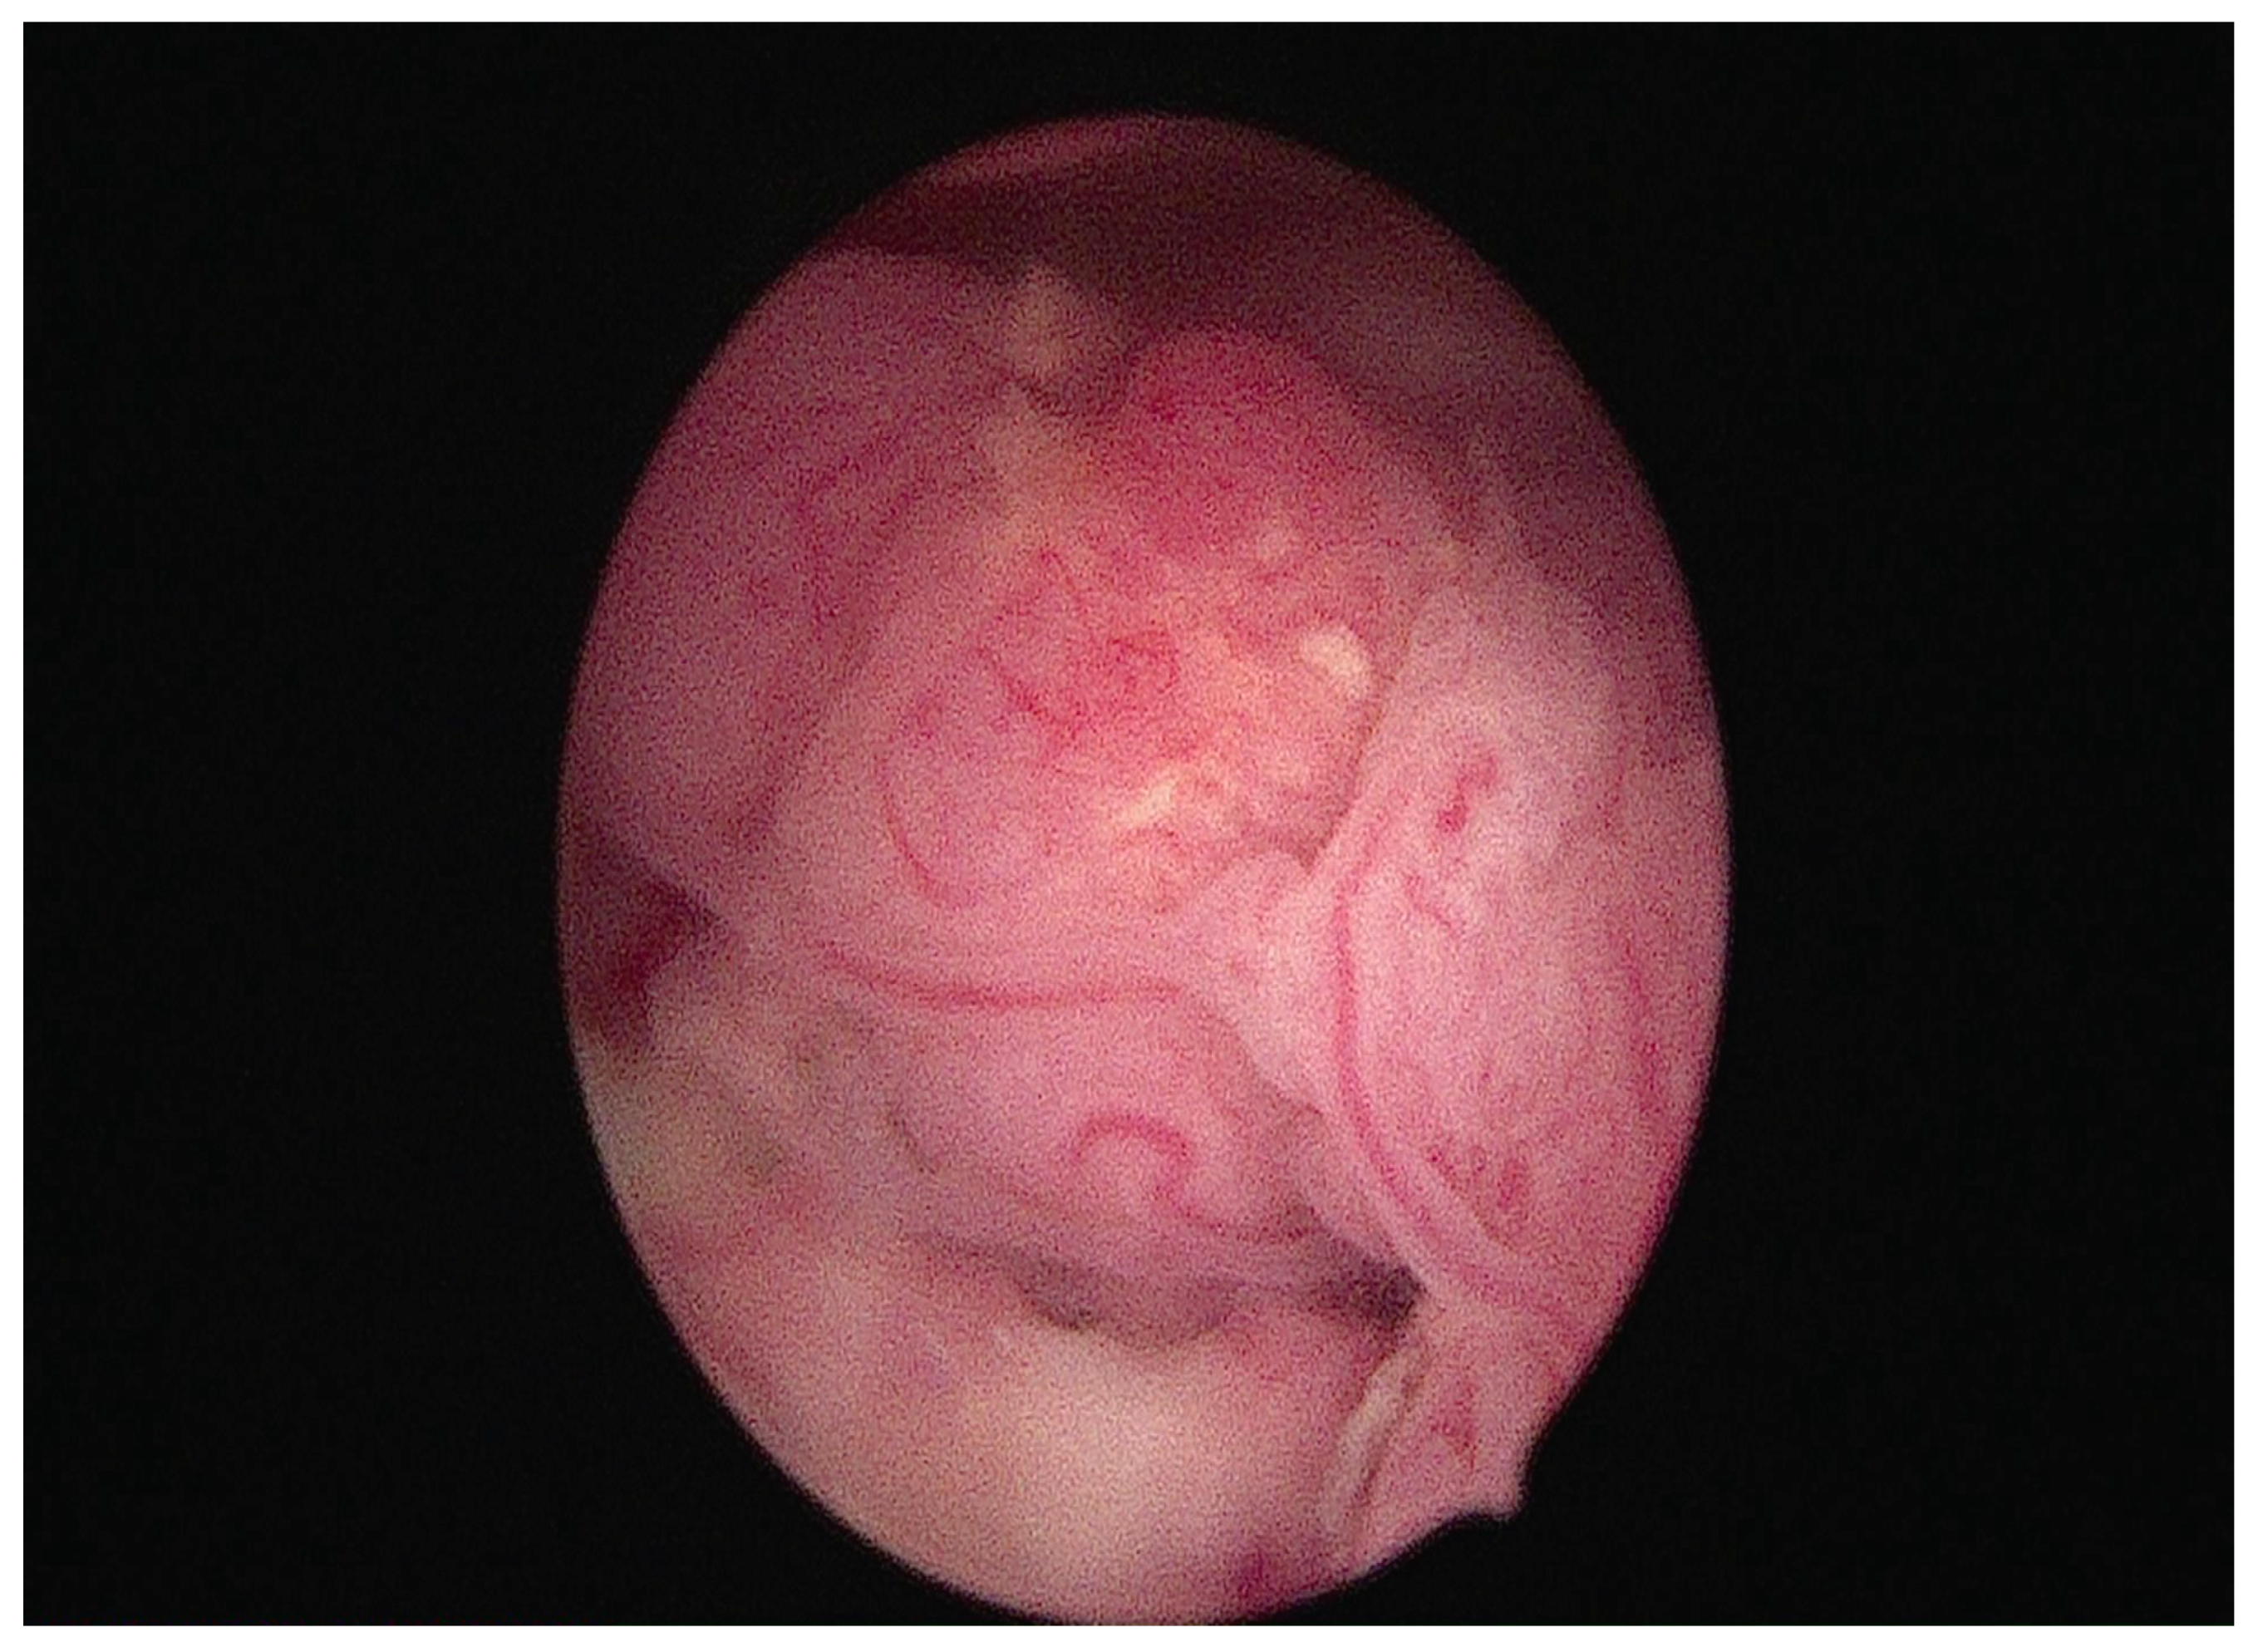

- Falcone, F.; Laurelli, G.; Losito, S.; Di Napoli, M.; Granata, V.; Greggi, S. Fertility preserving treatment with hysteroscopic resection followed by progestin therapy in young women with early endometrial cancer. J. Gynecol. Oncol. 2017, 28, e2. [Google Scholar] [CrossRef]

- Mazzon, I.; Corrado, G.; Morricone, D.; Scambia, G. Reproductive preservation for treatment of stage IA endometrial cancer in a young woman: Hysteroscopic resection. Int. J. Gynecol. Cancer 2005, 15, 974–978. [Google Scholar] [CrossRef] [PubMed]

| Laurelli G et al. Int J Gynecol Cancer. 2016 [21] | Italy, 2016 | long-term oncologic and reproductive outcomes | NA | - Pathological diagnosis of well-differentiated (G1) endometrioid endometrial cancer (EEC) with PR > 50% positivity at immunohistochemistry limited to the endometrium - Normal CA125 serum levels - No contraindication for progestin treatment - Over 18 years of age and under 45 years of age | Hysteroscopic resection (HR) to resect the tumor lesion, the endometrium adjacent and the myometrium underlying the tumor + Levonorgestrel intrauterine device (LNG-IUD) 52 mg. Duration: 6 months Follow-up: TVUS, serum CA125 and diagnostic hysteroscopy every 3 months, abdomen CT every 6 months. | - 85.7% complete regression, 9.5% persistent disease, 4.8% progressive disease - 10.5% recurrences - in the responders’ group, 92% pregnancy rate and 83% live birth rate |